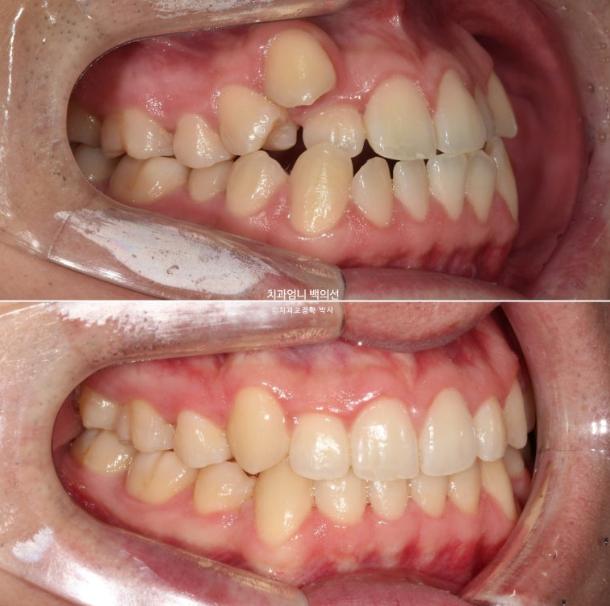

이제 전 후 비교 보겠습니다.

22.09~25.04